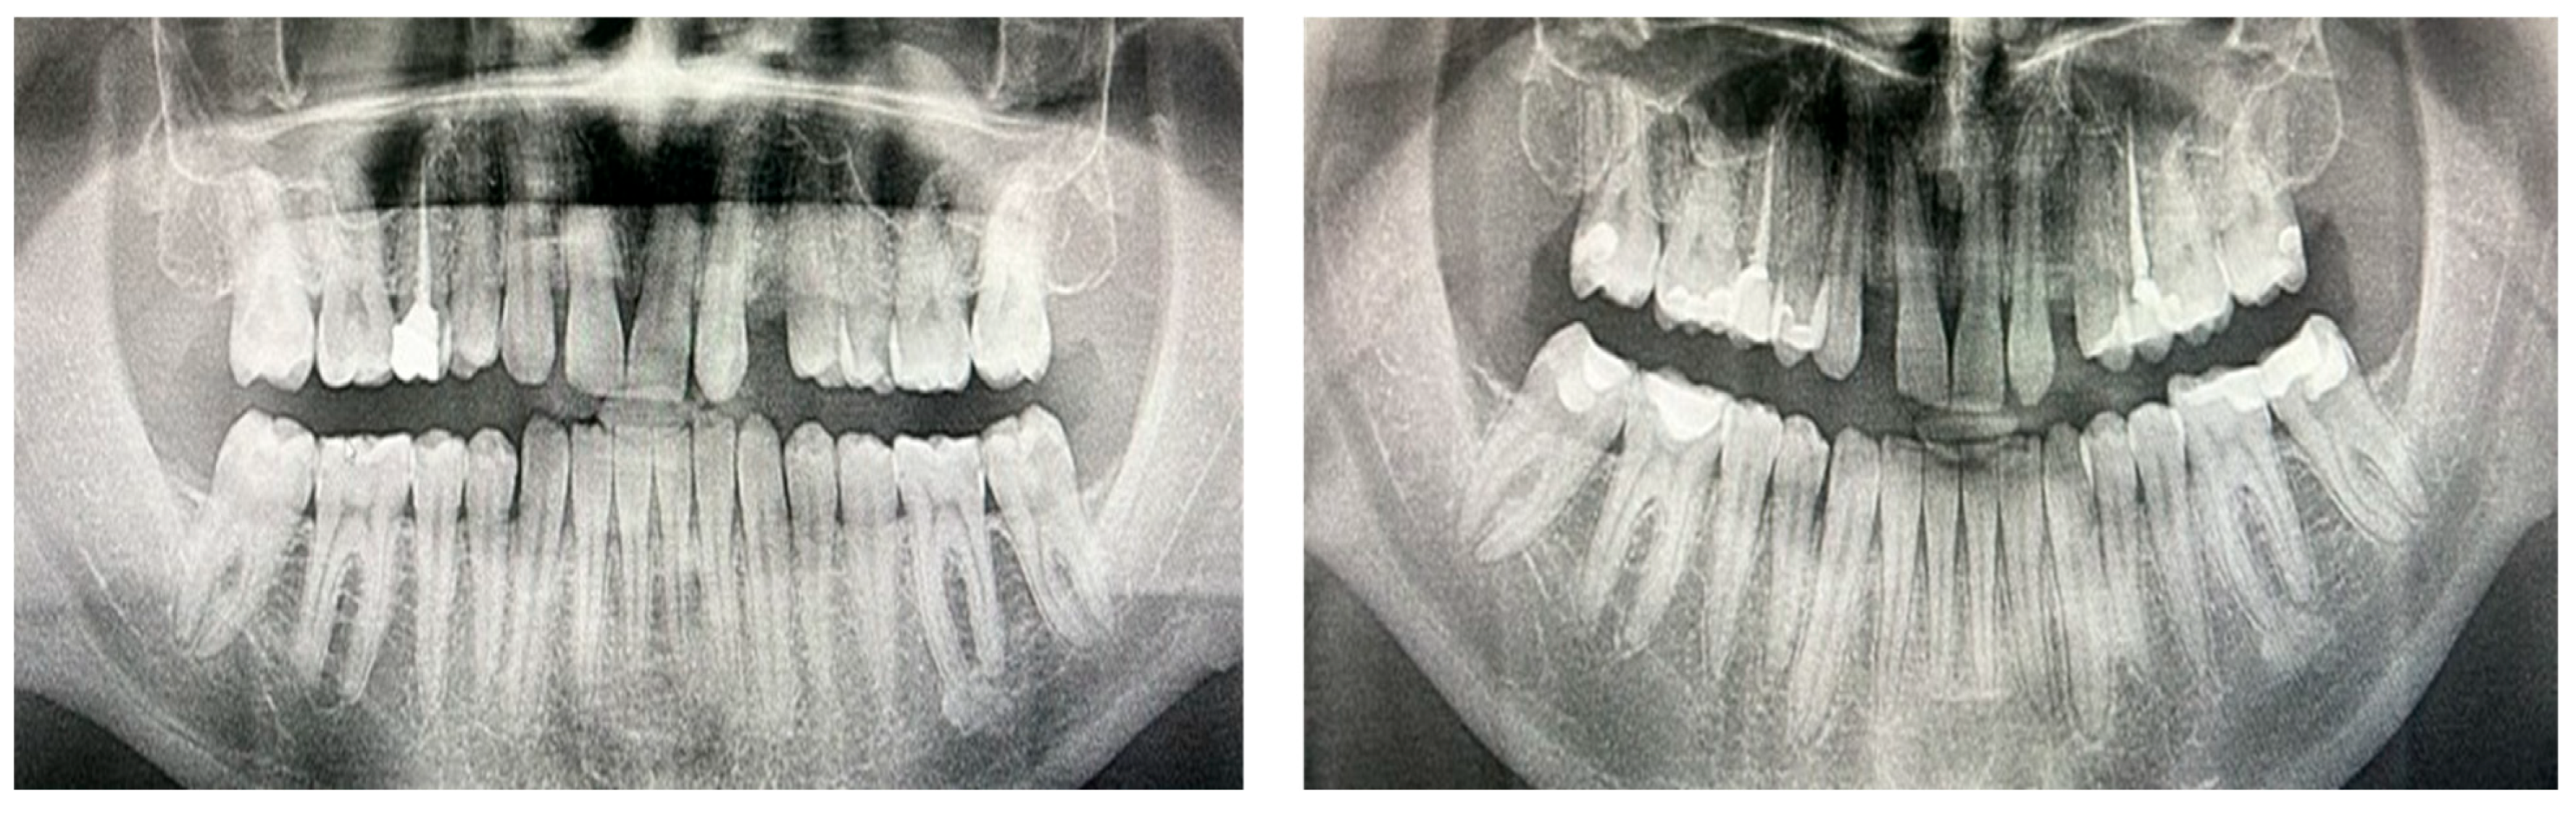

3.7. Representative Radiographs Demonstrate Subtle Post-Treatment Caries Changes